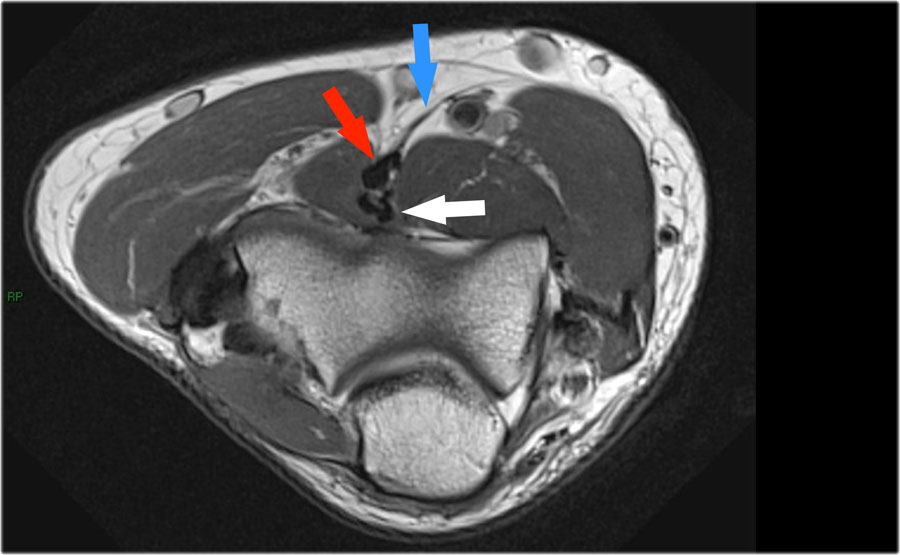

Khi quan sát trên lát cắt ngang (axial), chúng ta có thể nhận thấy sự hình thành gai xương khổng lồ.

Lưu ý rằng dây thần kinh trụ (mũi tên màu xanh) nằm cạnh các gai xương này và những bệnh nhân này có thể biểu hiện bệnh lý thần kinh trụ.